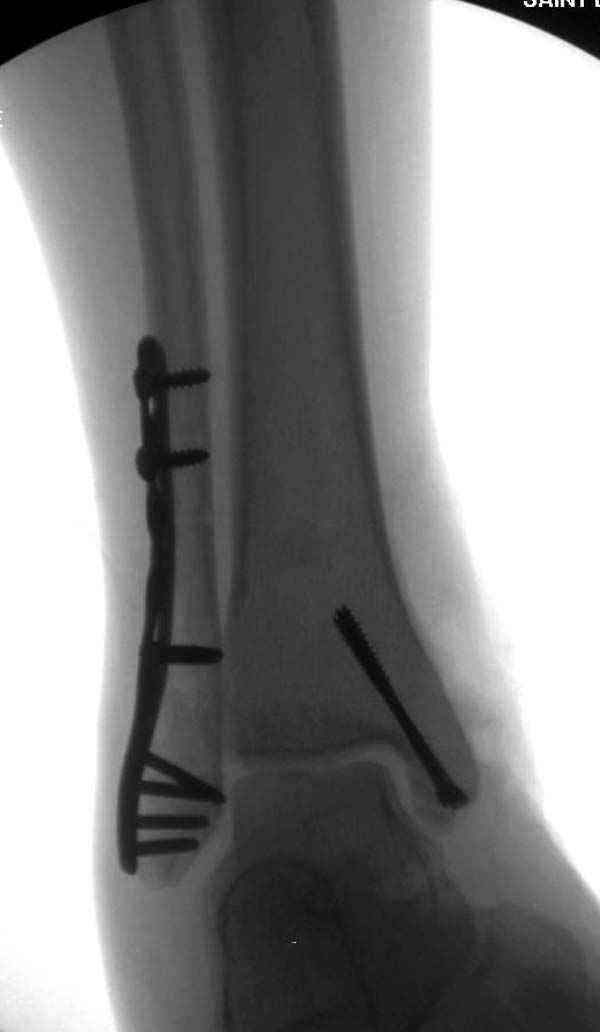

Описанная вами техника "Внутренняя лодыжка фиксирована по Веберу, наружная реконструктивной пластиной с наложением болта-стяжки" существует, но этот подход морально устарел, и применяется очень редко, только при отсутствии имплантов.

Нет первичных снимков, перелом очень низкий и под большим сомнением диагноз разрыва синдесмоза. Медиальная сторона отрепонирована на "хорошо" и, по-видимому, прорезание проволоки произошло во время операции. Без снимков трудно судить о высоте малоберцовой, а лодыжка находится в варусе. Лагирование получилось, но возле тонких шурупов передне-задний шуруп выглядит немного тяжеловато.

Во всех руководствах АО имеется описание техники применения низкопрофильных пластин 1/3 трубки, которые могут быть применены для фиксации наружной лодыжки. Фиксацию проводят кортикальными 3.5 мм шурупами, и если дистальная фиксация недостаточная, тогда усиливают конструкцию созданием hook plate. Сгибая конец пластины на последнем отверстии, внедряют его в дистальный отдел, и тем самым создается дополнительная фиксация.

Современные преконтурированные пластины не имеют таких недостатков, и разделяются на правые и левые, а также на латеральные и задние. Множественные дистальные шурупы 2.7 мм уменьшают подкожное раздражение, и такой имплант можно оставить на долгий срок без удаления.

Здесь несколько частных случаев: перелом голеностопа со сравнительными снимками и разрыв синдесмоза, а также медиальная Hook пластина.